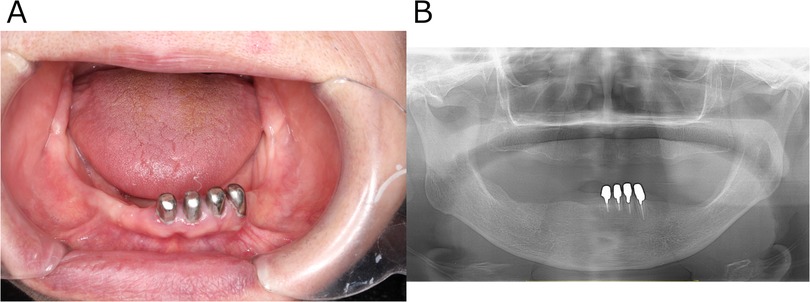

Her past medical history included lung cancer, meningioma, and hypertension. Regarding family/social history, her daughter had a history of depression; the patient herself ran a small business selling lactic acid probiotic beverages and lived with her husband and grandchild. Oral examination revealed no signs of infection such as swelling or redness of the gingiva around #33 and #34 (Figure 1A). Sometimes the pain subsided with loxoprofen. According to the short-form McGill pain questionnaire, she selected “Throbbing”, “Sharp”, “Cramping”, “Heavy”, and “Tiring-exhausting” as “moderate”, while she answered “burning” as “none” (6). The Somatic Symptom Scale-8 (SSS-8) score was 14, indicating a high burden of somatic symptoms (7). A panoramic radiograph revealed no organic abnormalities that could be the cause of her condition (Figure 1B). The referring internist noted that 12-lead ECG, Holter ECG, echocardiography, and chest CT showed no obvious abnormalities to explain her chest pain. Table 1 shows the blood test results from August 2022. Routine laboratory tests showed no abnormalities at first presentation. If this had been the acute phase of myocardial infarction, cardiac enzymes might have been elevated, but they were not in this case. In our department, she was diagnosed with “atypical odontalgia” affecting #33 and #34.

Figure 1. Clinical images obtained at the patient's initial visit to the psychosomatic dentistry clinic. (A) Intraoral photograph showing no structural or organic abnormalities that could explain the reported pain. (B) Panoramic radiograph likewise revealing no structural or organic abnormalities responsible for the pain.